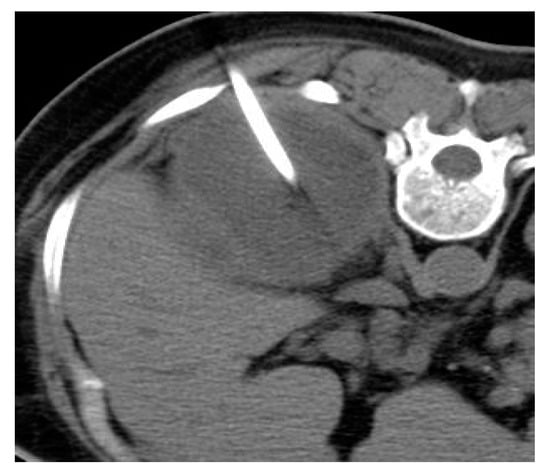

2.2. Renal and Perinephric Abscesses

| Renal abscesses | Round or geographic non-enhancing central fluid collection and enhancing rim. Perinephric fat stranding and thickening of Gerota’s fascia. |